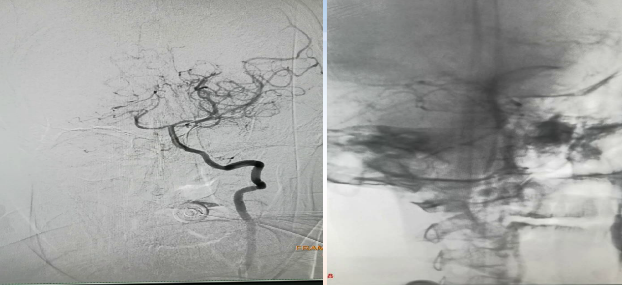

初始造影RICA起始位

病历夹什么径技·第152期|串联营病历夹:川陕大营_https://www.jmylbn.com_新闻资讯_第81张

初始造影后循环+LICA正位

病历夹什么径技·第152期|串联营病历夹:川陕大营_https://www.jmylbn.com_新闻资讯_第82张

手术过程

在Synchro微导丝与Rebar-18支架导管的辅助下顺利超选上去,借助Transend导丝使用球囊穿梭技术将Sprinter(3*15)球囊装入血管真腔中。

过程影像

病历夹什么径技·第152期|串联营病历夹:川陕大营_https://www.jmylbn.com_新闻资讯_第83张

病历夹什么径技·第152期|串联营病历夹:川陕大营_https://www.jmylbn.com_新闻资讯_第84张

由于guiding通过失败所以先处理近端,将Spider FX(5)保护伞置入进行了远端保护,近端放置了WALLSTENT支架,然后收伞,顺势将guider通过,结果其无法到达远端。

病历夹什么径技·第152期|串联营病历夹:川陕大营_https://www.jmylbn.com_新闻资讯_第85张

病历夹什么径技·第152期|串联营病历夹:川陕大营_https://www.jmylbn.com_新闻资讯_第86张

狭窄段用四个球囊后扩张,将cat6推过狭窄段,发现可能存在远端栓塞,因此将guider退了一下。

病历夹什么径技·第152期|串联营病历夹:川陕大营_https://www.jmylbn.com_新闻资讯_第87张

对侧造影显示,右侧大脑前动脉供血区血流较好。

病历夹什么径技·第152期|串联营病历夹:川陕大营_https://www.jmylbn.com_新闻资讯_第88张

接下来处理远端,Synchro微导丝与Rebar微导管的辅助下,选择置入Solitaire(4-20)支架,支架打开后使用抽拉结合的方式使血管再通。

病历夹什么径技·第152期|串联营病历夹:川陕大营_https://www.jmylbn.com_新闻资讯_第89张

取栓后造影如下:

手术评估

病历夹什么径技·第152期|串联营病历夹:川陕大营_https://www.jmylbn.com_新闻资讯_第90张

病历夹什么径技·第152期|串联营病历夹:川陕大营_https://www.jmylbn.com_新闻资讯_第91张

病历夹什么径技·第152期|串联营病历夹:川陕大营_https://www.jmylbn.com_新闻资讯_第92张